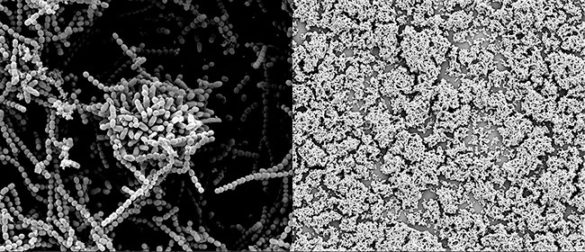

To do so, the researchers collected human milk carbohydrates, also called oligosaccharides, from a number of different donor samples and profiled them with a mass spectrometry technique that can identify thousands of large biomolecules simultaneously. Then they added the compounds to strep cultures and observed the result under the microscope. This showed that not only do some of these oligosaccharides kill the bacteria directly but some also physically break down the biofilms that the bacteria form to protect themselves.

In a pilot study, Townsend’s lab collected five samples. They found that the sugars from one sample nearly killed an entire strep colony. In another sample, the sugars were moderately effective while the remaining three samples exhibited a lower level of activity. In a follow-up study, they are testing more than two dozen additional samples. So far, two broke down the bacterial biofilms and killed the bacteria, four broke down the biofilms but did not kill the bacteria and two killed the bacteria without breaking down the biofilms.